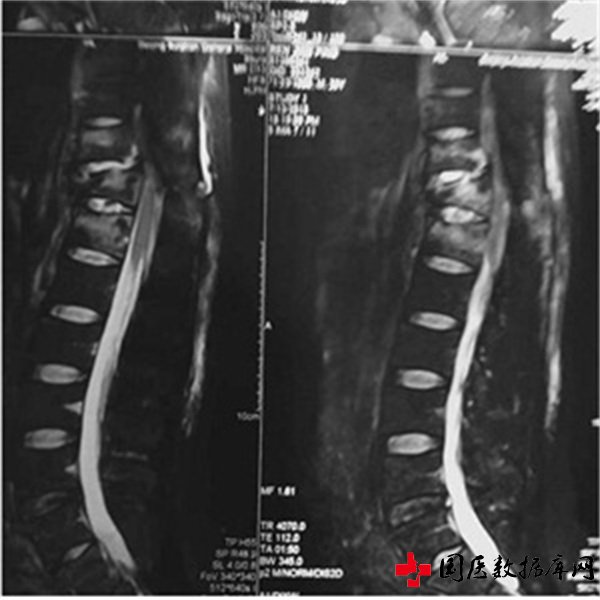

患者病例;任某,甘肃平凉人,外伤所至脊髓损伤(胸12)截瘫4年,不能行走,左腿稍为能动一下,右腿脚一点都动不了,经治疗三个月,可以扶单双杠行走。